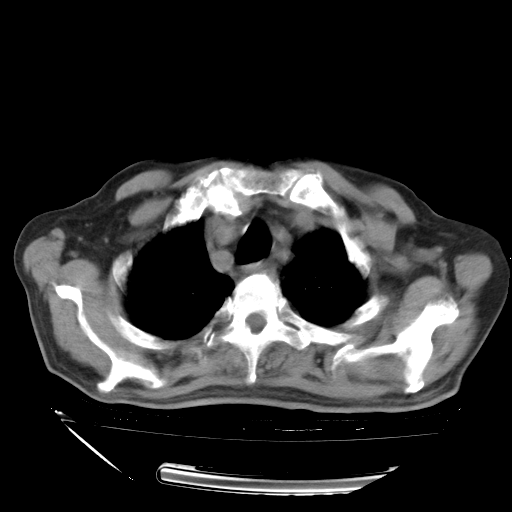

经过24天治疗,岳父的病情基本稳定。生活基本可以自理,可以下床活动。呼吸困难早已消失。体温基本正常。

只是甲强龙用80mg时血小板升到正常,改为60mg后又降到63×10*9/L。

主要治疗甲强龙80mg×14天,60mg×10天;同时抗结核(异烟肼+利福平+乙胺丁醇)。环磷酰胺0.1 tid 10天。

特别感谢胡教授、高管、桃子版主给出关键的治疗建议。桃版把所有肺部影像和全部临床资料请所在医院呼吸科、感染病科、结核科、临床免疫科专家会诊。临床免疫科专家制定了完整的治疗方案。